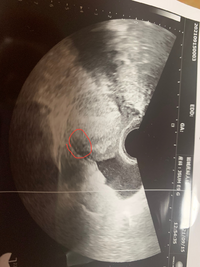

胎嚢がいびつ 妊娠4週と3日で本日エコーを みたら胎嚢の形がいびつで切迫 Okwave

妊娠4週3日 以後妊娠5週0日まではGSは毎日1mmずつ大きくなります 妊娠5週目以降は、GSの成長が人によって異なります 排卵後 23日目 妊娠5週2日までにGS内に卵黄嚢(YS)が確認できます YSの大きさが5mm以上の場合、流産の可能性があります 排卵後 26日目数えかたも正確でないのですが、最終の生理は 11月19日開始でした! 排卵日は不明で、周期は某サイトで33日と算出されています また、某サイトで週数計算すると、私的には5週目かと思っていたのですが、4週3日でした! 私も胎嚢の大きさが心配です さて、当たり前ですが週4勤務ということは毎週必ず週3日が休みなわけです。 そうなると、 必然的に時間に余裕が生まれてきます。 なんせ、 今まで土日にやらねばできなかったことを水曜日の休みにすることができるんですからね。

と思って、生理予定日4日前に試しに検査薬をしてみたらうっすら陽性! そこから毎日少しずつ濃くなり、生理予定日にはくっきり陽性。 お盆になるため念のために4w3dで病院へ。 たぶんこれでしょう~とのことで、胎嚢確認になりました。 次回は2~3週後。うちの会社では1ヶ月は43週間で計算します。 なぜかというと1年365日を12か月でわると一ヶ月平均日 になります。それを7日で割ると一ヶ月平均週間となります。 よって便宜上43週間となります。 週4日勤務は月172日で17日になります。日 * の間で 週 3 日・1 日 4時間 務は 平日 のみです シフトは自由に組み合わせられます。 例えば1 日7時間× 週 3 日× 4 週間=8 4時間など *休暇・休 日